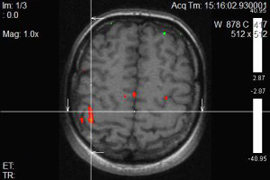

Ֆունկցիոնալ ՄՌՏ գնահատում է ուղեղի նեյրոնալ ակտիվության հետևանքով առաջացած հեմոդինամիկ փոփոխությունները, որի շնորհիվ հնարավոր է դառնում մեծ ճշգրտությամբ առանձնացնել ուղեղի կենտրոնները (խոսքի, տեսողության, շարժիչ և այլն): Չխորանալով մեթոդի ֆիզիկական սկզբունքների մեջ նշենք, որ ֆՄՌՏ-ի շնորհիվ կարելի է խուսափել կամ գոնե կանխատեսել հետվիրահատական նյարդաբանական դեֆիցիտները: Նախկինում նույնիսկ ամենաշնորհալի նյարդավիրաբույժները չէին կարողանում պատասխանել հիվանդների հարցերին, կապված հետվիրահատական բարդությունների հետ: Դա առաջին հերթին պայմանավորված է անատոմիական յուրահատկություններով, հարկ է նշել, որ պացիենտների գլխուղեղի ֆունկցիոնալ զոնաները լրջորեն կարող են տարբերվել բժշկական համալսարաններում օգտագործվող անատոմիական ատլասներում ներկայացված գլխուղեղի զոնաներից: Հետևաբար վիրաբույժի աչքի համար անտեսանելի կենտրոնները շատ հաճախ վնասվում էին և վիրահատությունից հետո պացիենտները դժվարանում էին ինքնուրույն տեղաշարժվել, կորցնում էին ինքնասպասարկման տարրական ունակությունները, խոսքի կարողությունը:

Այժմ նոր մեթոդի ներդրումով հնարավոր է նվազագույնի հասցնել նման ռիսկերը: Ինչպես նաև, ֆՄՌՏ մեթոդի ոչ ինվազիվության շնորհիվ հնարավոր է կատարել բազում գիտական աշխատանքներ, որպես փորձադաշտ օգտագործելով առողջ մարդկանց, չխախտելով որևէ էթիկական նորմատիվ: Այժմ ֆՄՌՏ մեծ գիտական կիրառություն ունի հոգեբուժության և հոգեբանության մեջ: «Փակված մարդու» համախտանիշի ժամանակ կատարված սենսացիոն գիտափորձերը հնարավոր դառձան միայն ֆՄՌՏ-ի շնորհիվ: Ստեղծվեց պարզագույն կապ այնպիսի պացիենտների հետ, ովքեր տարիներ շարունակ գտնվում էին կոմայի մեջ, և պարզ չէր արդյոք նրանք ընկալում են շրջապատող աշխարհը, լսում են իրենց հարազատների ձայները և վերջապես իմաստ ունի սարքերի միջոցով արհեստականորեն պահպանել նրանց կյանքը, թե` ոչ:

Նկարներում պատկերված է ձախ ձեռքի շարժիչ կենտրոնը, այն գտնվում է աջ կիսագնդի առաջկենտրոնական գալարում: